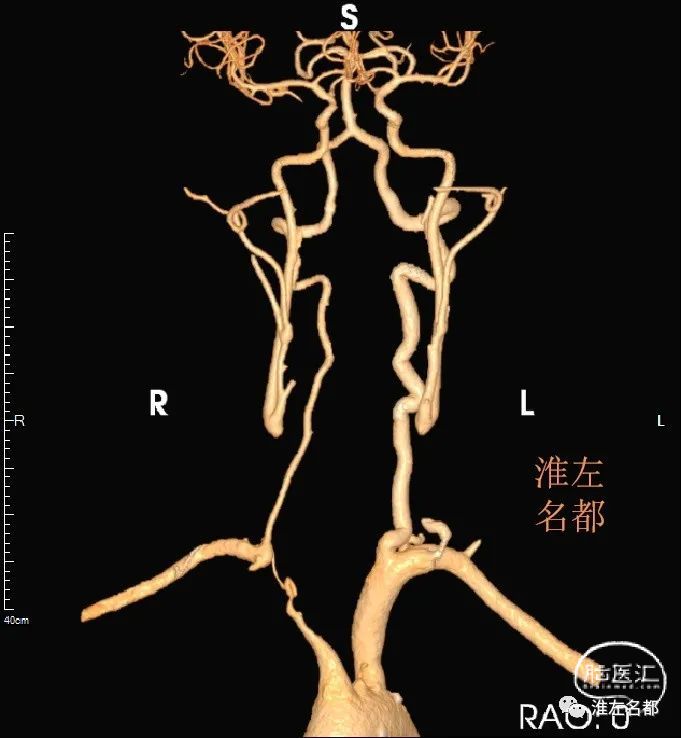

影像读片稳定期的多发性大动脉炎弓上血管闭塞cta和管壁mri

图片尺寸681x738